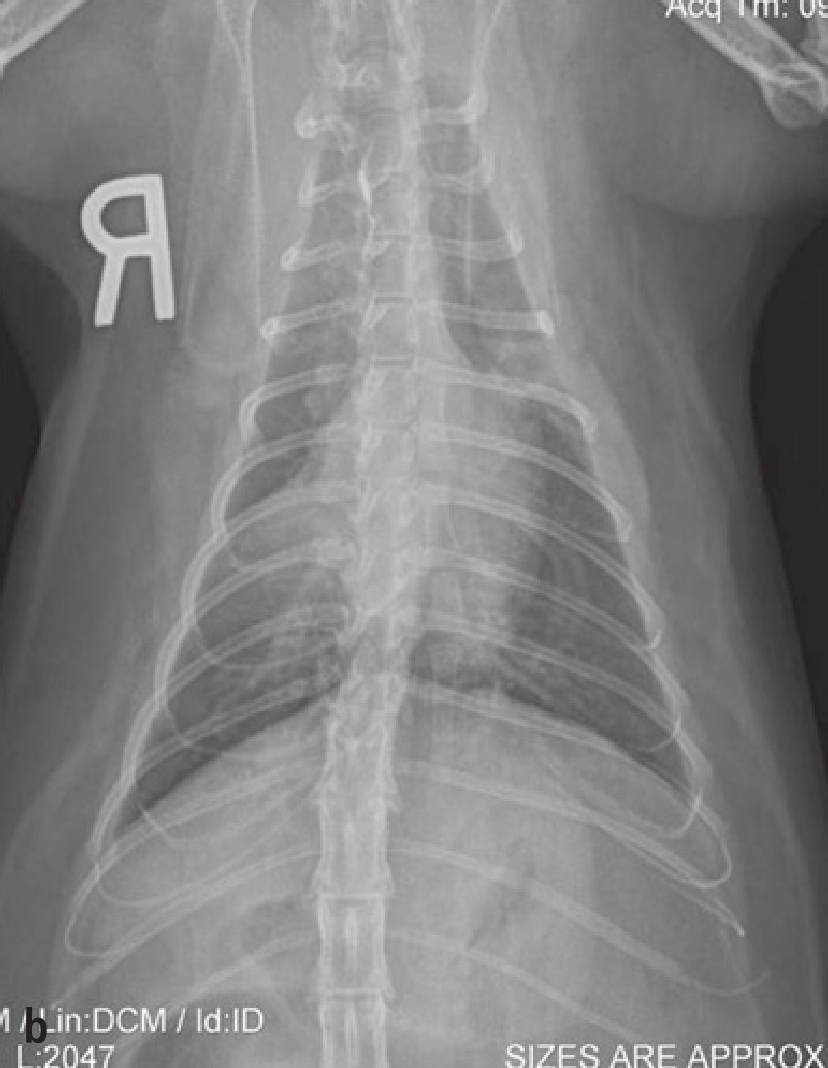

Jika pemeriksaan fisik menunjukkan adanya masalah saluran pernapasan, metode yang selanjutnya biasa dipilih adalah radiografi (x-ray) rongga dada untuk melihat ada tidaknya kelainan pada paru-paru dan jantung. Hasil radiografi akan diinterpretasikan oleh dokter hewan penanggung jawab, sehingga tidak perlu dipusingkan. Namun, sebagai gambaran, kucing yang asma bisa menunjukkan paling sering menunjukkan pola bronkhial, yaitu cincin putih atau dua garis putih seperti rel kereta api, menunjukkan adanya masalah pada bronkhus. Keanehan lain juga dapat terlihat, seperti hiperinflasi paru-paru karena kesulitan menghembuskan napas, dan kolaps lobus paru. Radiografi bisa sangat membantu mengerucutkan diagnosis, tetapi belum cukup untuk mengatakan seekor kucing kena asma. Pertama, sekitar 20% kucing dengan asma akan memiliki radiograf yang normal, sehingga radiograf yang tampak normal belum cukup untuk mengeliminasi kemungkinan asma. Kedua, radiograf asma sulit dibedakan dengan masalah bronkhus lain, seperti bronkhitis kronis karena infeksi.